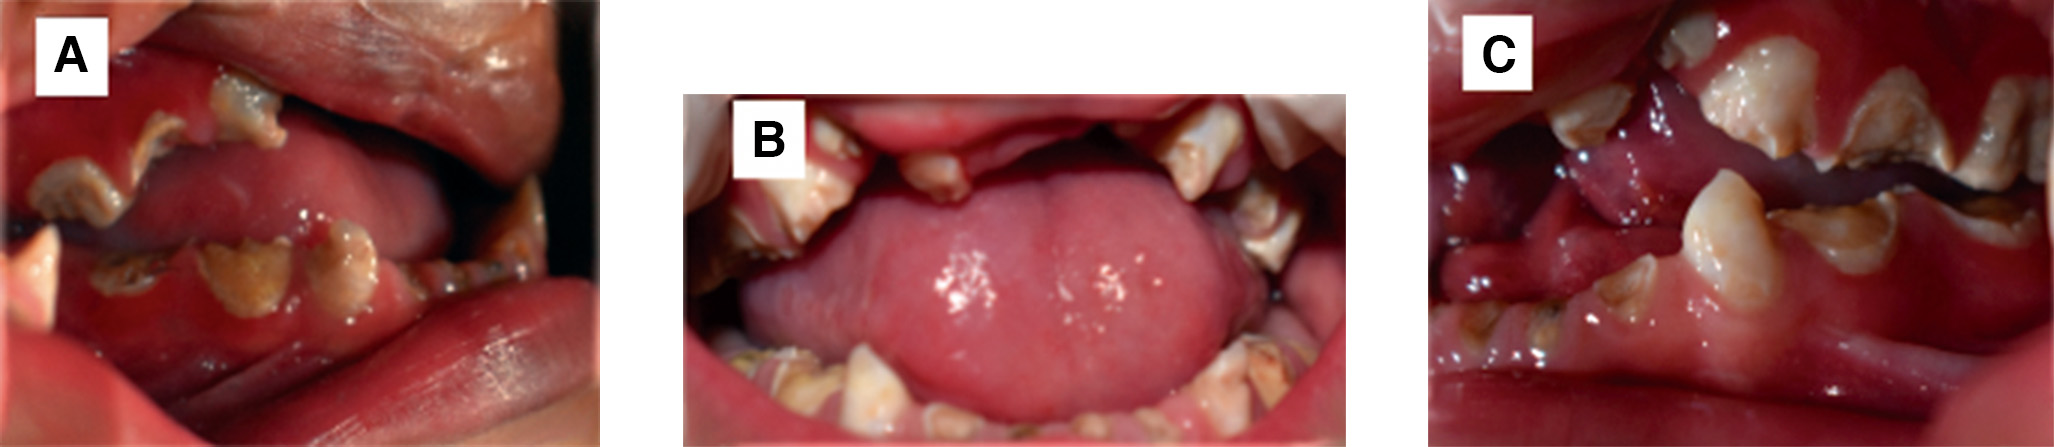

A la exploración intrabucal se encontró una hendidura completa bilateral en el paladar y la presencia de múltiples lesiones cariosas. (Figura 2 A, B y C). El paciente refirió dolor y sensibilidad sin necesidad de algún estímulo, asimismo, registró baja talla y peso de acuerdo con su edad. Tras una valoración detallada del comportamiento del paciente, se clasificó como Frankl I, según la escala de conducta. Mantener al paciente libre de estrés e incertidumbre fue el propósito del caso para que fuera ejecutado de manera exitosa, por lo que se decidió trabajar bajo anestesia general.

Figura 2. A, B y C. Fotografías intraorales iniciales.